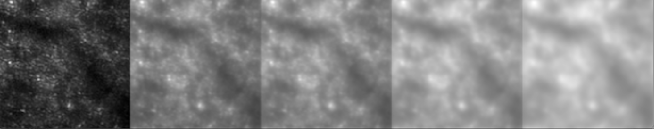

We apply the entropy assessment on different part of the field to compare the image quality between the two methods. We define an image quality ratio based on entropy assessment between the linear and non linear method on the registration made up the same selected images. This ratio is close to 1 at the center part of the field and is around 1.07 at the corners of the field of view to indicate first the reliability of the NLR method and a better efficiency far from the center part of the image where is applied the rigid rotation correction of the linear method. We conclude in the same way using the kurtosis assessment that indicates values from 1 to 1.1 from center to corners. Nevertheless, sharpness assessment gives a value of 0.95 on the entire field of view (i.e., in favor of the linear method). We find that entropy assessment seems to match better with our subjective estimation of the quality, showing interesting close linear property in respect with the image corrugation and, being a robust criterion also with significant changes of the template. Fig. 6 shows an example of super-resolution obtained after the registration on the selected images from the sequence. The resolution displayed is four times better by comparison to the best raw image.

We successfully applied the NLR method to determine the optical flow and the moving direction vectors using a current SD-OCT infrared imaging system at the Ichilov Hospital in Tel Aviv (Heidelberg infrared reflectance imaging flash fundus observed at 870 nm with a resolution of 11 m and a frame rate acquisition of 9 images per second). Fig 7 presents one image extracted from the entire sequence shown in the movie. The NLR method is applied on the entire sequence made up 160 images. Then, we applied a filter to cut-off low frequencies in the Fourier domain to compensate for the intensity fluctuations [27, 13]. We follow proper motions, distinguishing the artifacts due to the intensity variation from the optical flow. In this set of data, we are not able to follow the blood cell motions inside the arteries or the veins. We show that the subjective impression of motions inside the veins or arteries come from the variations of luminosity during the measurements. The proper motions derived from the structures are compatible with heart beats (10 beats along the sequence) in agreement with the frame rate cadence of the detector. The optical flow accuracy is validated by the sub-pixel registration reliability (about 11 m on the field).